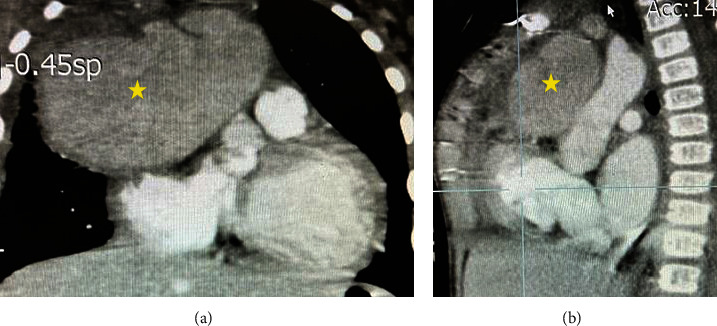

主动脉假性动脉瘤是一种罕见的疾病,其特征是局部的跨壁破坏和主动脉扩张,在儿科人群中非常罕见。它主要是由先前的心血管手术引起的,如主动脉缩窄修复、主动脉瓣置换术和主动脉下膜切除术。我们提出一个独特的病例主动脉假性动脉瘤手术后修复膜周围室间隔缺损在一个19个月大的男孩谁提出发烧作为唯一的症状。术后第30天开始发热,实验室检查结果异常,白细胞(WBC) 28.3 × 109/L,中性粒细胞百分比68%,血小板计数880 × 109/L,红细胞沉降率(ESR) 200 mm/h, c反应蛋白3+阳性。超声心动图示升主动脉内一巨大囊性肿块(5 × 4.8 cm),压迫上腔静脉。基于这一发现,我们怀疑诊断为主动脉假性动脉瘤。经心脏计算机断层血管造影确诊,患者在深低温和循环停止下接受紧急手术修复主动脉假性动脉瘤。不幸的是,我们的病人在手术后不久就死了。

Aortic pseudoaneurysm, a rare condition characterized by localized transmural disruption and dilatation of the aorta, is very rare in the pediatric population. It is primarily caused by previous cardiovascular procedures such as aortic coarctation repair, aortic valve replacement, and subaortic membrane resection. We present a unique case of aortic pseudoaneurysm following surgery to repair a perimembranous ventricular septal defect in a 19-month-old boy who presented with fever as the sole symptom. The fever started on the 30th day after the surgery, and the patient exhibited abnormal laboratory results, including a white blood cell (WBC) count of 28.3 × 109/L, neutrophil percentage of 68%, platelet count of 880 × 109/L, erythrocyte sedimentation rate (ESR) of 200 mm/hour, and 3+ positive C-reactive protein. Echocardiogram revealed a large cystic mass (5 × 4.8 cm) in the ascending aorta, compressing the superior vena cava. Based on this finding, a diagnosis of aortic pseudoaneurysm was suspected. The diagnosis was confirmed through cardiac computed tomographic angiography, and the patient underwent emergent surgery for the repair of the aortic pseudoaneurysm under deep hypothermia and circulatory arrest. Unfortunately, our patient died shortly after the surgery.